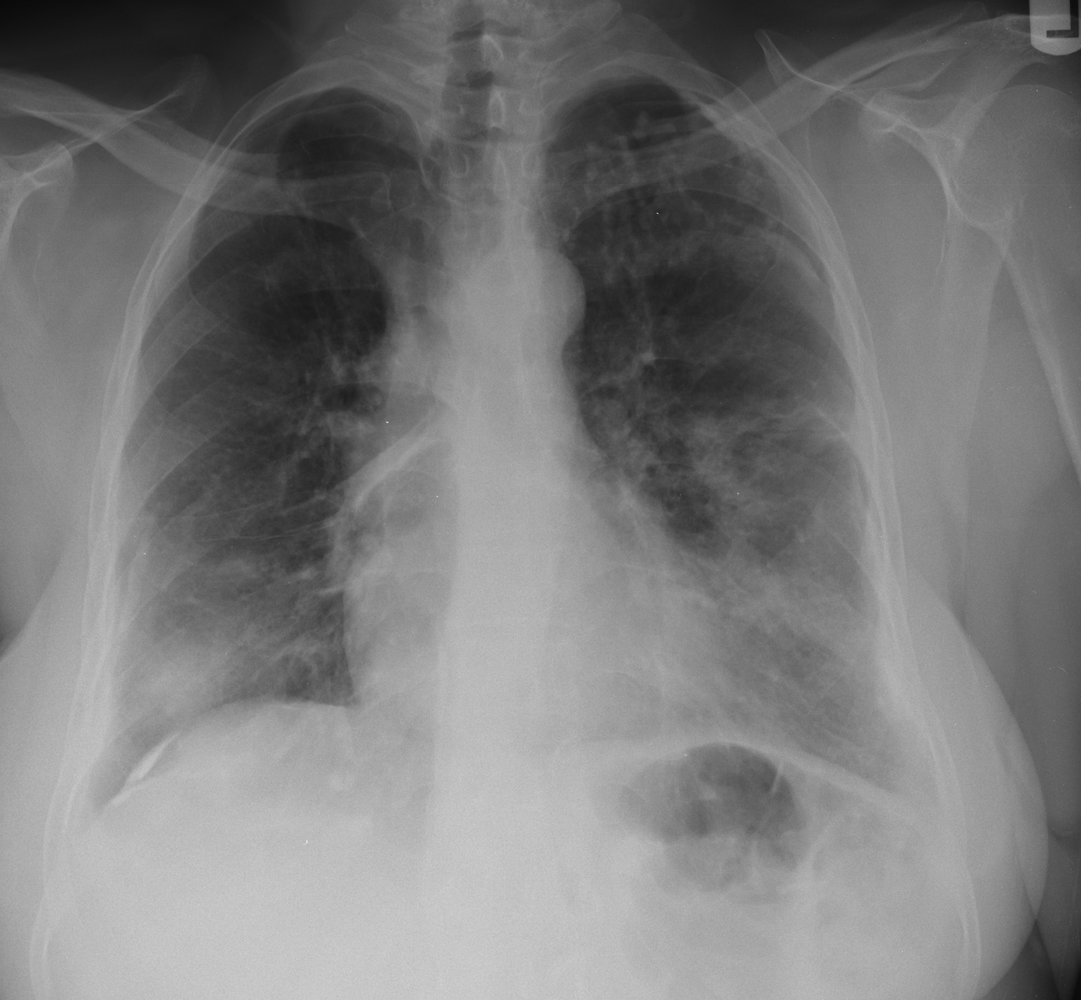

• Chest x-ray

• Signs of interstitialfibrosis (e.g., diffuse bilateral opacities, predominantly in the lower lobes)

• Pleural abnormalities (e.g., pleural plaques and pleural thickening) may be seen.